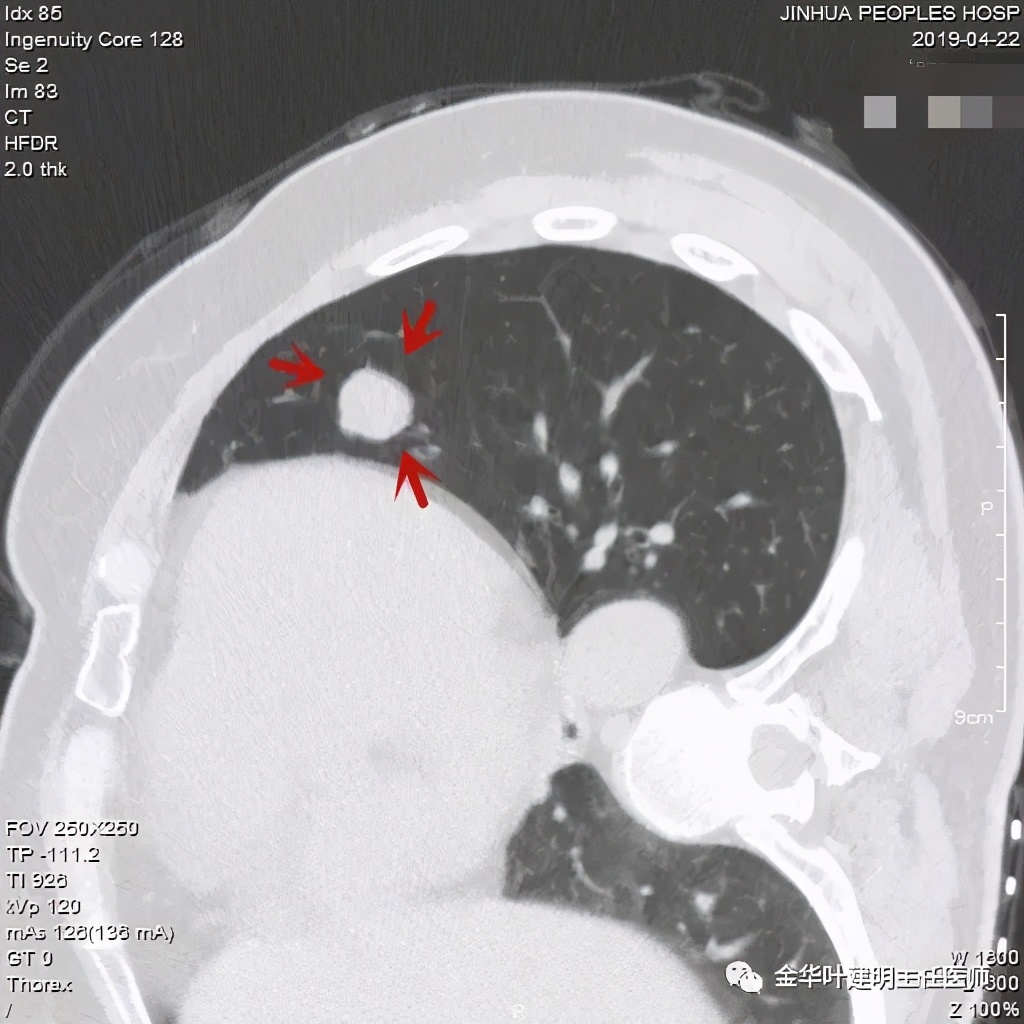

直径约2.4厘米,密度欠均,血管贴边,增强轻度强化。单从描述看,恶性可能性较大。我们再来看看图像:

可见右上叶占位,我们现在知道了结果以后回头看,发现病灶的边缘在各个层面都是过于光滑(绿色箭头所示)。血管紧贴病灶边走行(桔色箭头所指),是不是有侵犯看不清楚,若是靶扫描加重建可能会更清楚点。支气管感觉也是贴着病灶走,但有的层面是不是截断,也不看的不太清楚。有的层面见局部有点状高密度(蓝色箭头所指),是不是错构瘤的局部钙化呢?若是纵隔窗又是如何?

上图示病灶